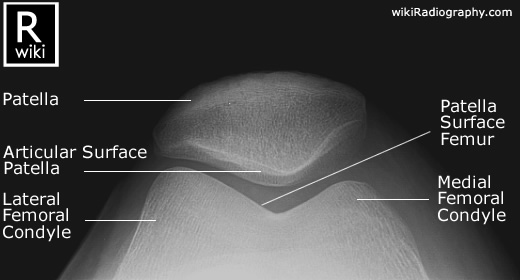

Spine Radiographic Anatomy

| AP view (Cervical) | AP view (Thoracic) |

![]() |

| AP view (Lumbar) | AP view (Sacrum) |

1) http://www.wikiradiography.net